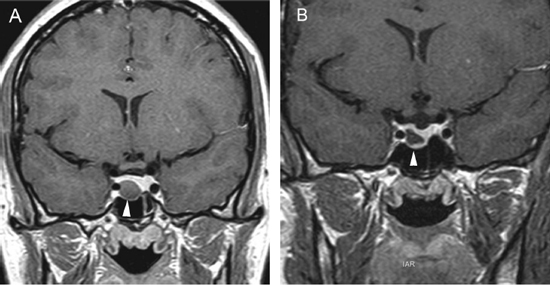

Figura 10A y B. Microadenoma pituitario (prolactinoma), secuencias T1W antes y después de contraste, cortes coronales. Sin Gadolinio el tumor tiene señal similar a la glándula pituitaria. La secuencia T1W post Gadolinio, muestra la glándula contrastada y a izquierda un tumor no contrastado, (hipointenso) de 7 mm (punta de flecha). Características de la imagen del adenoma pituitario